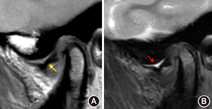

在横断位T2WI图像上显示双侧颞下颌关节髁突的最大径层面(内外极连线),垂直于髁突最大径层面定位(而非翼外肌走行方向)(图5A)[2],单侧定位层数为奇数,如9~13层,保证至少1层经过髁突中心。参考扫描参数如下,视野:12 cm×12 cm~18 cm×18 cm;矩阵:256×256~332×288;扫描层数:9~13层/侧;层厚:2~3 mm;层间距:0.2~0.3 mm;激励次数:2~3;重复时间:2 000~3 000 ms;回波时间:10~30 ms[3,4,5,6,7,8,9]。

注:黄线为扫描平面,数字为扫描层数

在横断位T2WI图像上显示双侧颞下颌关节髁突的最大径层面(内外极连线),平行于髁突最大径层面定位(图5B),单侧定位层数为奇数,7~11层,保证至少1层经过髁突中心,两侧定位线避免交叉。扫描参数如下,视野:12 cm×12 cm~18 cm×18 cm;矩阵:256×256~332×288;扫描层数:7~11层/侧;层厚:2~3 mm;层间距:0.2~0.3 mm;NEX:2~3;重复时间:2 000~3 000 ms;回波时间:10~30 ms[3,4,5,6,7,8,9]。